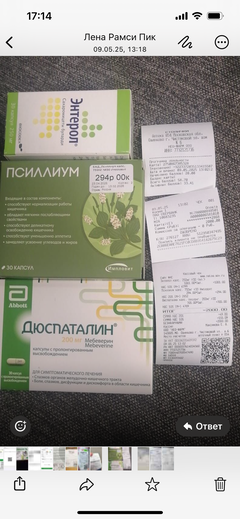

Была куплена в питомнике взрослой. У Масяни начались проблемы с кишечником и она стала подтекать и все пачкать. Надо отдать должное хозяевам - ее обследовали вдоль и поперек - как говорили местные врачи, сдавали много анализов но диагноза так и не поставили.

Ярко выраженная болезненность в области крестца, на обезболе полегче. По результатам приема невролога проведена миелография - множественная компрессия, возможно опухоль, возможно грыжа, нужно удалять...